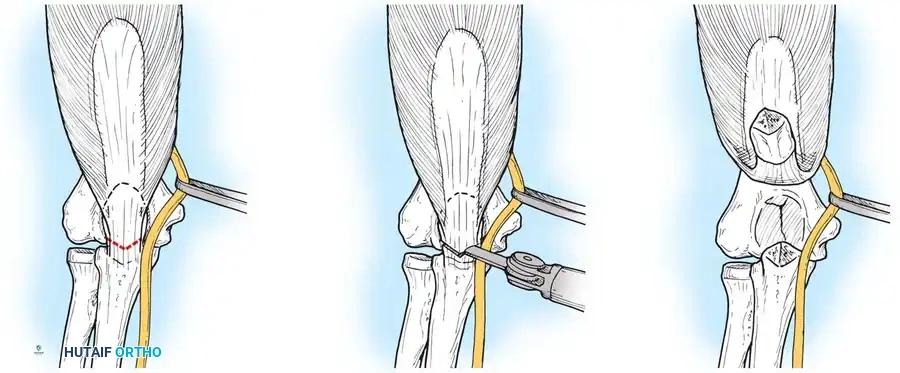

Surgical Steps:

4. Osteotomy: A chevron (V-shaped) osteotomy is planned at the bare area of the greater sigmoid notch. It is initiated with a thin-bladed oscillating saw and completed by levering with an osteotome. This creates an irregular subchondral fracture that aids in anatomic reduction and rotational stability during closure.

5. Exposure: The proximal olecranon fragment and attached triceps are reflected proximally, exposing the articular surface.

Image

Fig. 8: Intraoperative progression of the olecranon osteotomy, demonstrating the chevron cut and subsequent proximal reflection of the extensor mechanism.